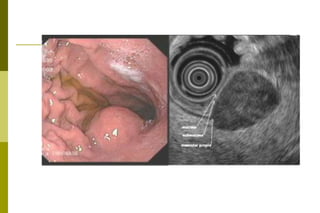

Outros:Doença de Ménétrier: é uma hiperplasia das células mucosas superficiais da mucosa gástrica, mais comum em homens na 4a à 6a décadas. Na realidade, não é gastrite (isto é, não há inflamação), nem hipertrófica (o que há é uma hiperplasia das células epiteliais). A causa é desconhecida

Outros:Doença de Ménétrier:é uma hiperplasia das células mucosas superficiais da mucosa gástrica, mais comum em homens na 4a à 6a décadas. Na realidade, não é gastrite (isto é, não há inflamação), nem hipertrófica (o que há é uma hiperplasia das células epiteliais). A causa é desconhecida